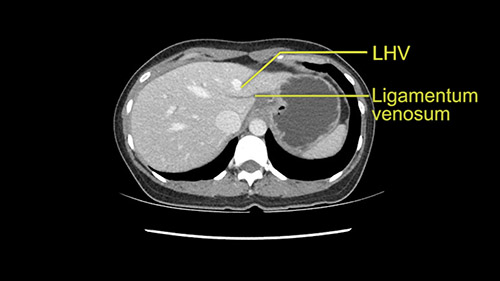

Anatomically, to plan for a left lateral segmentectomy, it’s relatively easy as far as liver surgery goes. I know that I'm going to be looking for the left hepatic vein which will be divided at some point either towards the end at the back near the vena cava or through the middle of the left lateral segment.

I generally take the ligamentum venosum to get access to the left hepatic vein. In this case, not necessarily but we certainly need to think about it.

The other option of course is to do an anatomical left hepatectomy. In that case, I will start mobilizing of course the left lobe and try to find the ligamentum venosum, take it down and go around the left hepatic vein. I think, importantly in these cases and in this case, as you can see in the venous phase, that’s clearly a moment to stop. Because the left hepatic vein is pretty close to the middle hepatic vein as sometimes it is so you may need to dissect a little bit the parenchyma on top of the left hepatic vein to be able to go around the left hepatic vein safely.